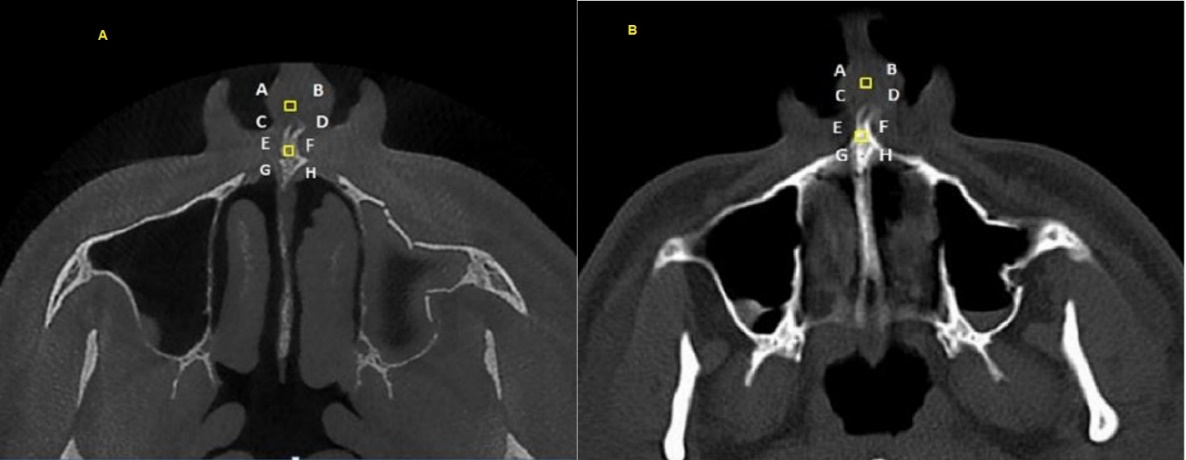

Four points were considered for each tissue and based on the anatomic landmarks in the area, they were matched in the CT and CBCT images. To this end, both images of each patient were simultaneously evaluated, and the corresponding points in that area were determined. For example, to evaluate the nasal area in the axial cross-section, squares measuring 2 mm on each side were used at a distance of 2 mm from the area in front of the anterior nasal spine (Figure 1); as another example, in order to evaluate the enamel in patients with central incisors, 4 points on one line were considered at a distance of 1 mm from the incisal edge. The alveolar crest emergence point was used on both images to evaluate the pulp in the axial cross-section.

Figure 1. Use of the anterior nasal spine in the axial cross-section to evaluate a 2-mm square for the evaluation of nasal soft tissues at a distance of 2 m in front of it; A. CBCT view; B. CT view.